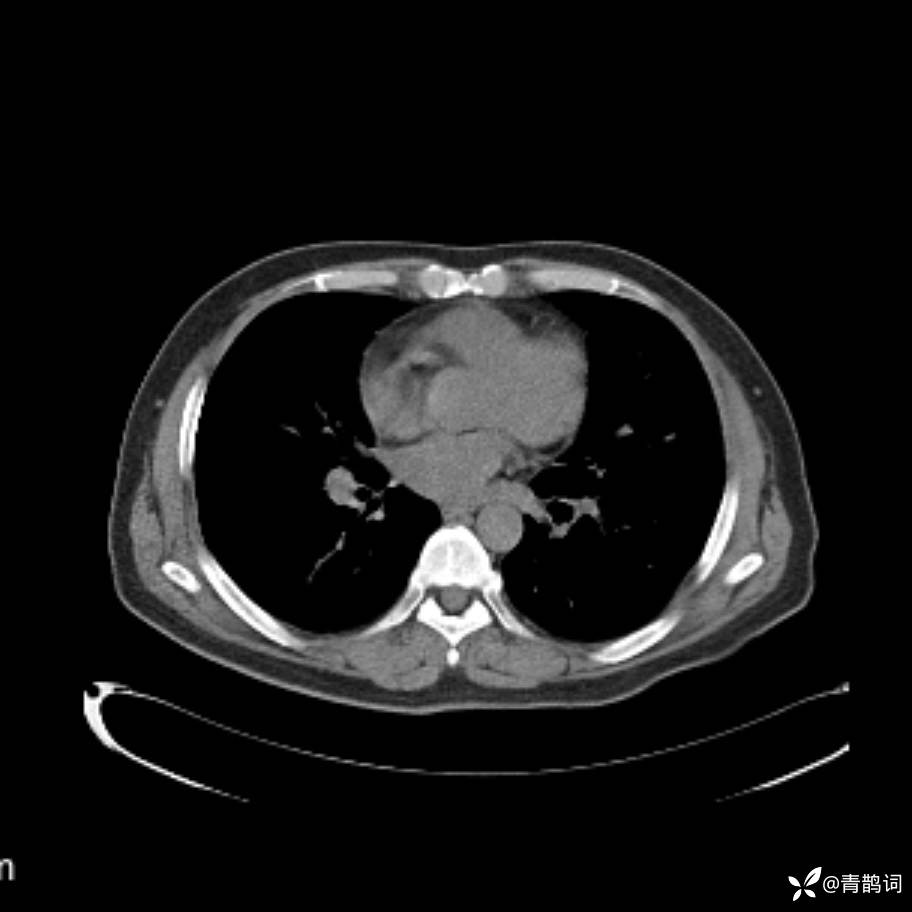

患者年龄:30岁。

患者性别:男。

简要病史:左颜面部肿胀2年,反复咳嗽咳痰,逐渐加重。

结合病史及影像学表现,期待评论区各位老师各抒己见~

木村病 (14)